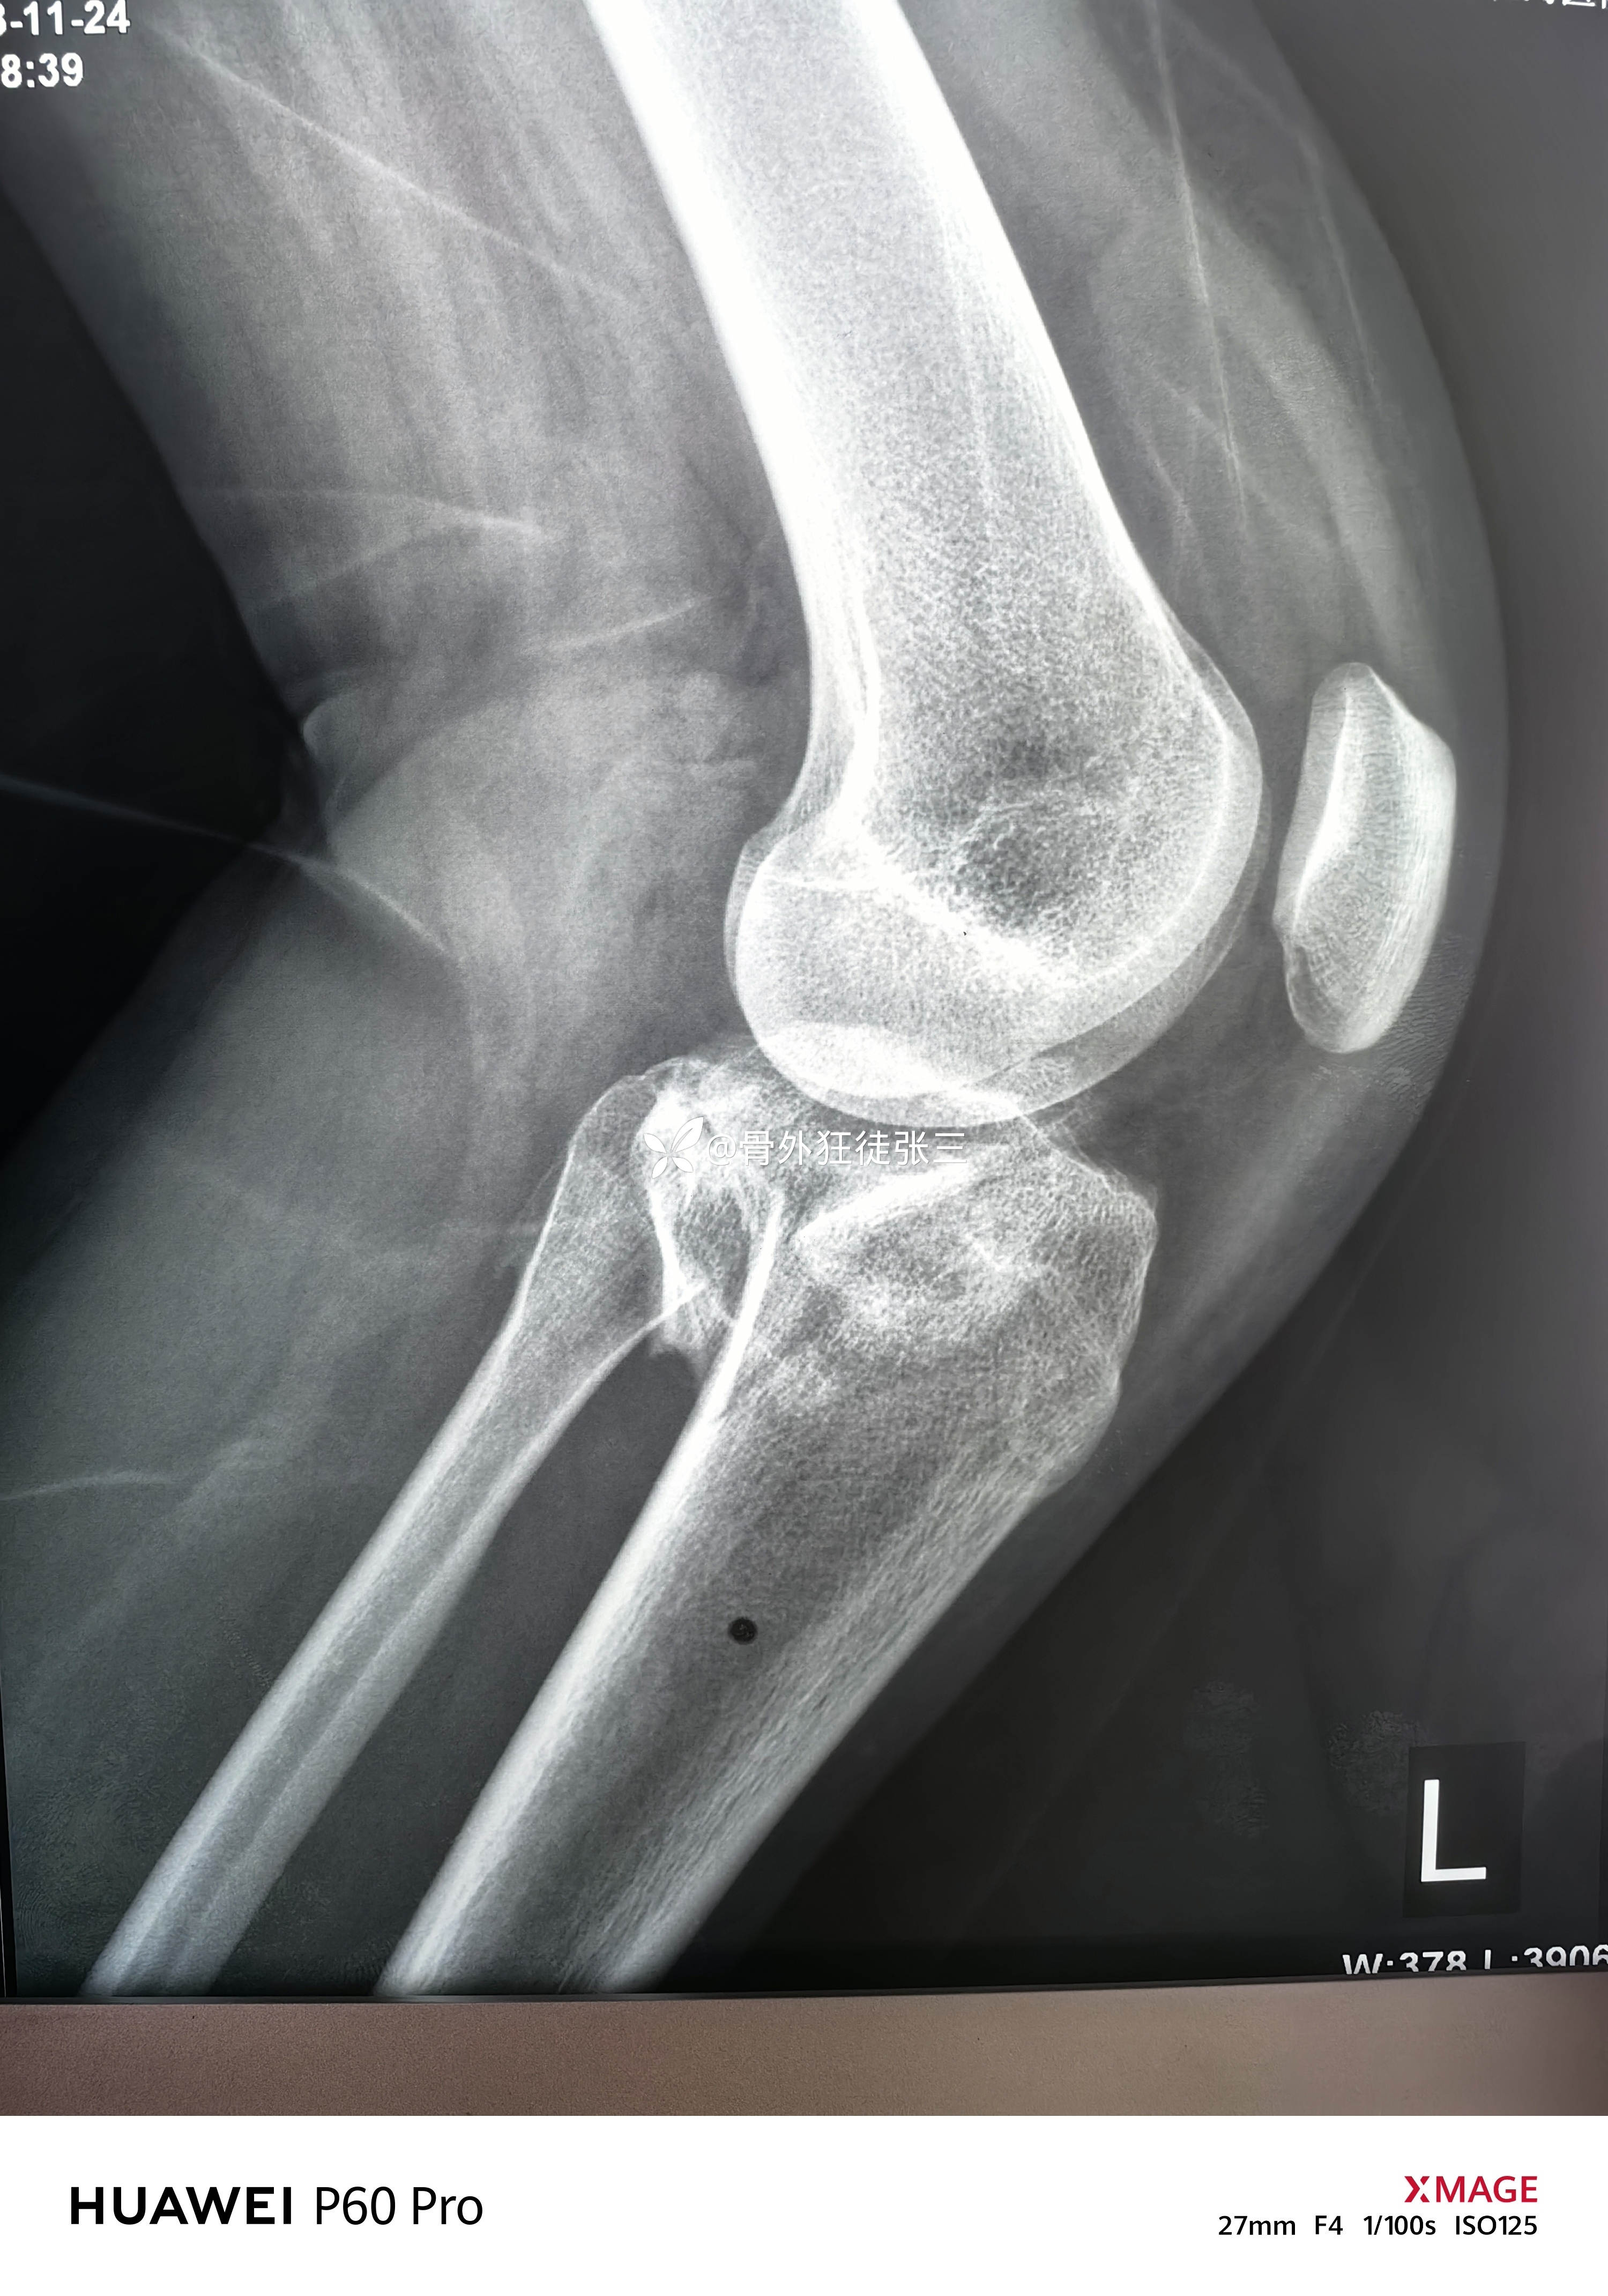

胫骨平台骨折术后,腓总神经损伤,

患者性别:女

患者年龄:19岁

主诉:右胫骨平台骨折术后膝、踝关节活动和感觉障碍3月余。

2023.12.08,在当地医院行胫骨平台骨折手术

第一次手术后复查